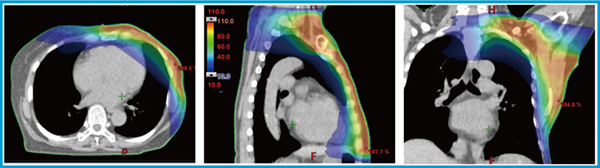

2.治療計画手法

治療計画手法は,SIBによる腫瘍床ブーストと同様である。ただし,アイソセンタの数はArc Geometry Toolの推奨に基づいて決定している。VMATを用いることで,胸壁と鎖骨上領域の接合部に線量の不均一が生じることなく,均一な線量分布で治療を行うことが可能となる(図2)。

図2 鎖骨上・腋窩リンパ節領域へのVMATを用いた線量分布図

胸壁と鎖骨上領域の接合部に対しても均一な線量分布が確認できる。